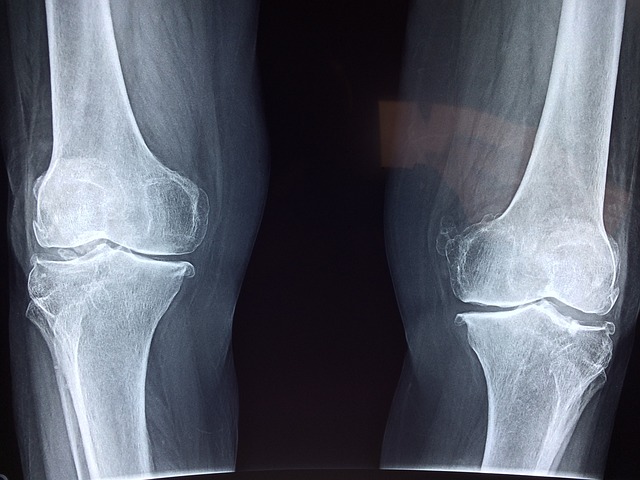

Gips jest tradycyjnym rozwiązaniem stosowanym w przypadku złamań kości lub innych poważnych urazów. Jest to sztywny materiał, który otacza i stabilizuje uszkodzoną część ciała. Gips jest skutecznym sposobem na unieruchomienie kości i umożliwienie jej prawidłowego zrastania.